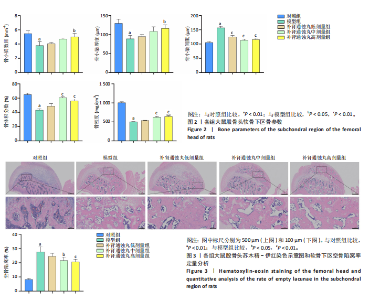

.1 实验动物数量分析 参加实验SD大鼠数量为50只,均进入结果分析。 2.2 Micro-CT检测结果 通过Micro-CT观察各组大鼠股骨头区域骨质变化,见图1。乙醇会导致大鼠股骨头软骨下骨骨量明显减少,骨小梁排列出现紊乱、稀疏等状况,而补肾通蚀丸能够改善上述情况,且呈现一定的剂量效应。模型组骨小梁厚度、骨小梁数目、骨体积分数、骨密度较对照组显著降低(P < 0.01),模型组骨小梁间隙较对照组则显著升高(P < 0.01)。经过不同剂量补肾通蚀丸干预后,各项指标均出现不同程度的逆向改变;其中,与模型组比较,补肾通蚀丸高剂量组骨小梁厚度、骨小梁数目、骨体积分数、骨密度均显著升高(P < 0.05),骨小梁间隙则显著降低(P < 0.05);与模型组比较,补肾通蚀丸中剂量组骨体积分数、骨密度显著升高(P < 0.05),骨小梁间隙则显著降低(P < 0.05);而补肾通蚀丸低剂量组仅在骨小梁间隙指标上较模型组显著降低(P < 0.05),见图2。 2.3 苏木精-伊红染色结果 与对照组比较,模型组大鼠股骨头出现核固缩现象,多见脂肪空泡,部分骨小梁出现断裂、变细;补肾通蚀丸低、中、高剂量组骨细胞核固缩和脂肪空泡较模型组有所减少;在整体结构方面,补肾通蚀丸低剂量组骨小梁变细现象较模型组未见明显改善,但断裂情况有所改善;而补肾通蚀丸中、高剂量组骨小梁断裂、变细情况较模型组均明显改善,见图3;在空骨陷窝率方面,模型组较对照组显著增高(P < 0.01);补肾通蚀丸中、高剂量组较模型组有所降低(P < 0.05),见图3。 2.4 免疫组化染色结果 与对照组比较,模型组NLRP3、Caspase-1、消皮素D蛋白表达明显增强,而Runt相关转录因子2、骨钙素、Ⅰ型胶原蛋白表达显著降低(P < 0.01);与模型组比较,补肾通蚀丸中、高剂量组能够显著降低NLRP3、Caspase-1、消皮素D蛋白表达,且促进Runt相关转录因子2、骨钙素、Ⅰ型胶原蛋白表达(P < 0.05),而补肾通蚀丸低剂量组骨钙素、Ⅰ型胶原蛋白表达有所上调(P < 0.05),其余指标则无明显差异(P > 0.05),见图4,5。 2.5 ELISA检测结果 与对照组比较,模型组大鼠血清中白细胞介素18和白细胞介素1β水平显著增高(P < 0.01);与模型组比较,补肾通蚀丸各剂量组大鼠血清中白细胞介素18和白细胞介素1β水平均显著降低(P < 0.01),且以一定剂量依赖方式递减,见图6。 2.6 Western blot检测结果 与对照组比较,模型组大鼠股骨头组织中NLRP3、cleaved-Caspase-1、Caspase-1、消皮素D、消皮"